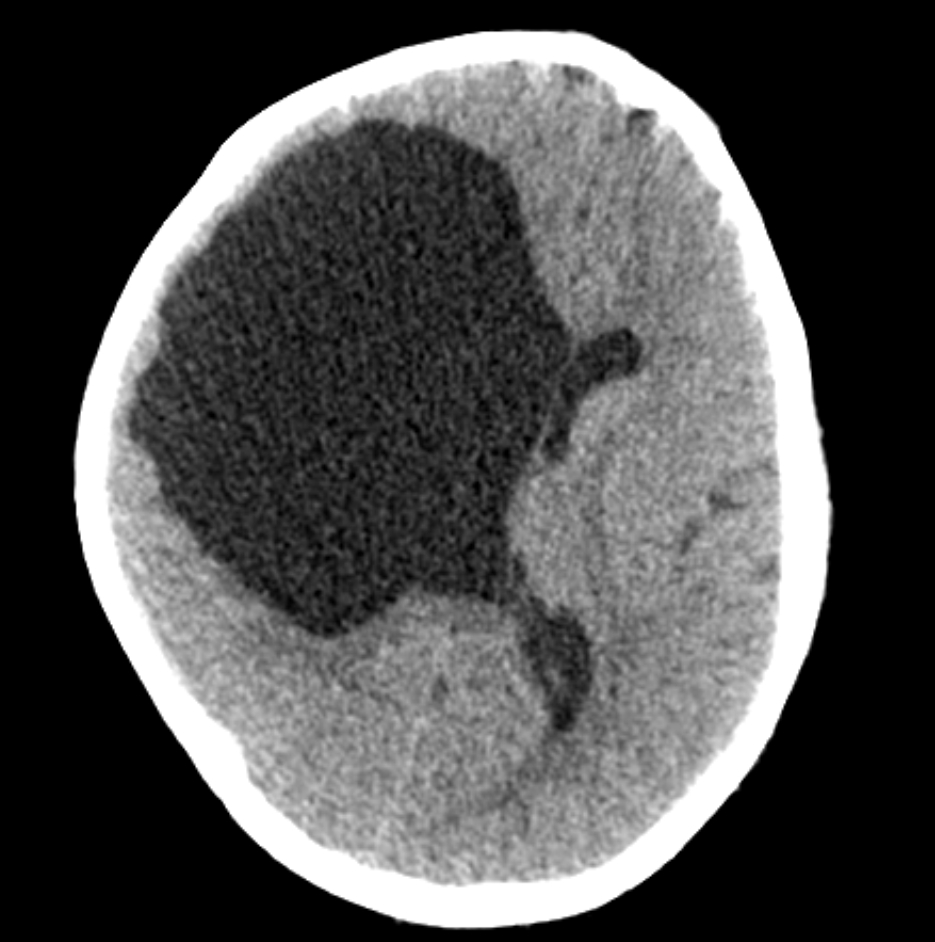

Hydrancephaly

• Destruction of cerebral hemispheres and replaced with fluid

• Basically bilateral large MCA infarcts

• Absence (may have some small residual tissue) of the cerebral hemispheres

• The thalami and posterior fossa are typically preserved

• Falx typically present -it is an infarct not midline cleavage issue!

• DDx - severe hydrocephalus, L1CAM disease, oters